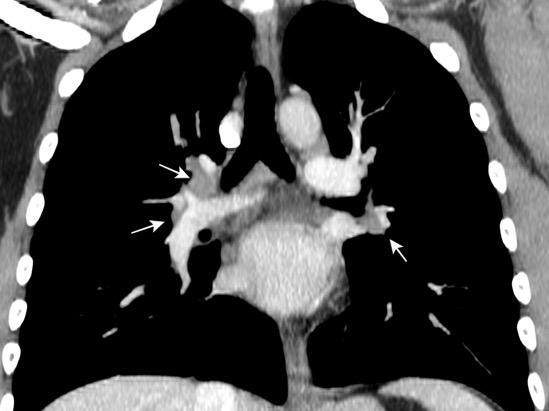

Silicosis secundaria al pulido con chorro de arena. Tejidos ”Denim”. (vaqueros, etc.)

Marchiori E et al. Conglomerated masses of silicosis in sandblasters: High-resolution CT findings. Eur Radiol 2006

Alper F,, et al. CT findings in silicosis due to denim sandblasting. Eur Radiol. 2008

Conglomerado silicótico